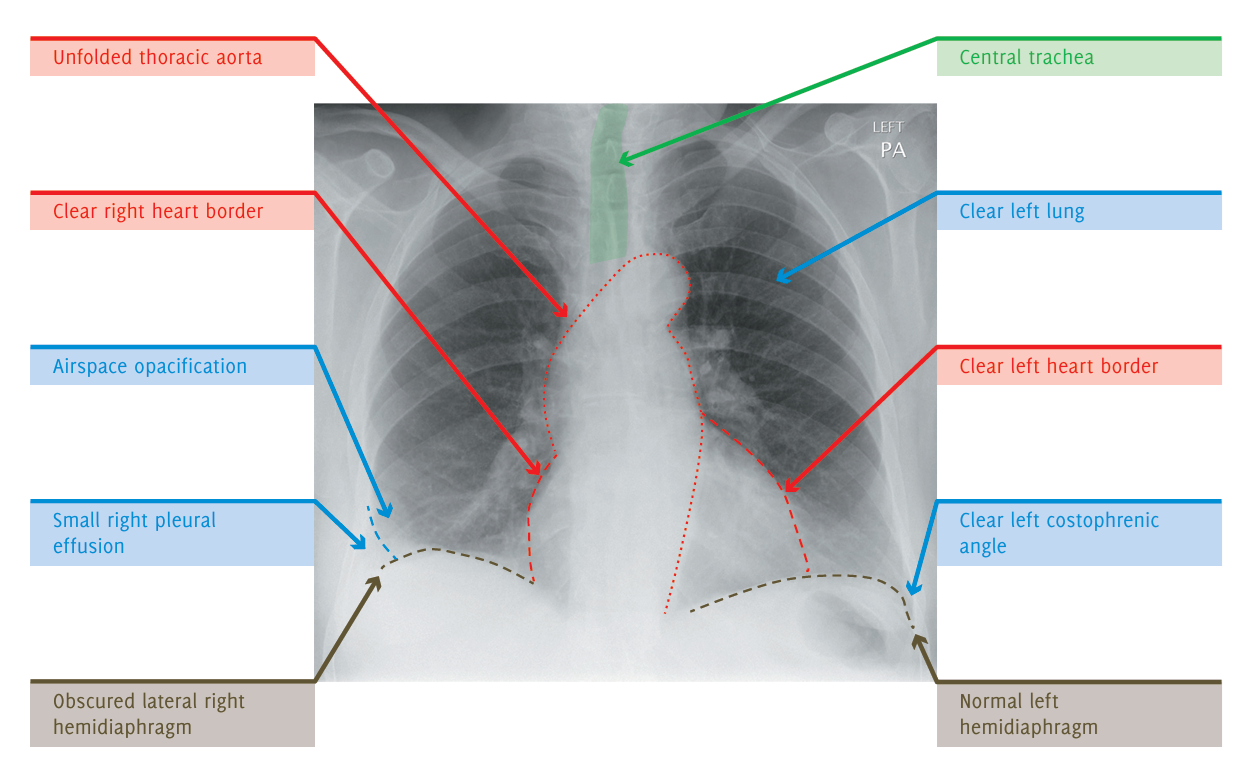

Un hombre de 70 años que vive en un hogar residencial se presenta a la sala de emergencias con aumento de la confusión. Tiene tos productiva y fiebre.

Tiene antecedentes médicos de hipertensión, angina e incapacidad cognitiva leve. Tiene un historial de 25 paquetes-año de tabaquismo. En el examen físico, presenta saturaciones de 89% en aire y fiebre con una temperatura de 38.8°C. Se observa matidez a la percusión y estertores gruesos en el lóbulo superior derecho. Se solicita una radiografía de tórax para evaluar posible neumonía o colapso.

La radiografía muestra una consolidación heterogénea en el lóbulo superior derecho, compatible con neumonía. La consolidación tiene un margen inferior relativamente abrupto, consistente con la fisura horizontal, lo que indica que se trata de neumonía del lóbulo superior derecho. Una opacidad focal en esta región puede representar una consolidación focal o una masa. De manera incidental, también se observa una hernia de hiato.

Las pruebas iniciales de laboratorio pueden incluir hemograma (FBC), análisis de electrolitos y función renal (U/Es), hemocultivos y proteína C reactiva (CRP). También se puede realizar un cultivo de esputo.

El paciente debe ser tratado con antibióticos adecuados para neumonía adquirida en la comunidad, y se debe realizar una radiografía de tórax de seguimiento en 4-6 semanas para asegurarse de que haya resolución. Los antibióticos pueden ser orales o intravenosos dependiendo de la gravedad de la neumonía (según CURB-65).

Si la opacidad focal en el lóbulo superior derecho no se resuelve, sería apropiado realizar una tomografía computarizada (TC) de tórax y abdomen con contraste intravenoso para evaluar un posible tumor pulmonar. También sería útil revisar imágenes previas y las notas del caso para verificar si ya existía alguna anomalía en esta área anteriormente.